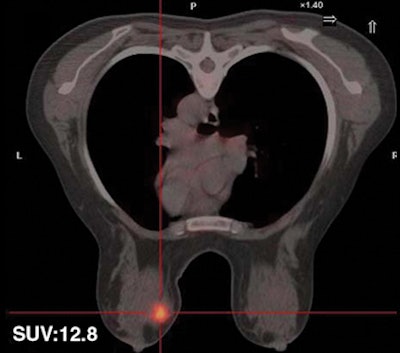

| Fifty-five-year-old woman with ductal infiltrating adenocarcinoma measuring 15 mm in maximum transverse diameter. Axial fused PET/CT images obtained with patient in prone position at time point 1 (above) and time point 2 (below) show corresponding standard uptake values. All images courtesy of the American Roentgen Ray Society. |

| Thirty-two-year-old woman with ductal infiltrating adenocarcinoma measuring 18 mm in maximum transverse diameter. Axial fused PET/CT images obtained with patient in prone position at time point 1 (above) and time point 2 (below) show corresponding standard uptake values. |